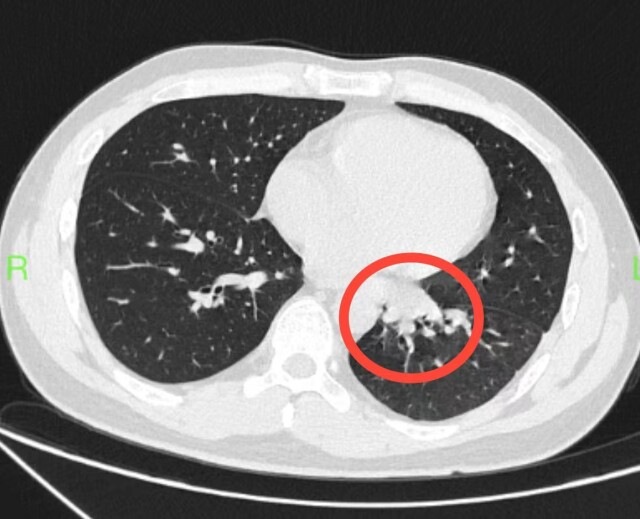

为寻求进一步治疗,小王跟随父母来到湖南省人民医院胸外一病区佘科霖主任医师处就诊,完善肺部增强CT显示,小王患上的是左下肺隔离症(肺内型),病灶动脉血供来自于胸降主动脉,手术治疗是首选。

肺隔离症,这是什么疾病?从CT上看,仿佛多长了个肺似的。

“肺隔离症是一种少见的先天性肺部发育畸形,是在胚胎时期肺发育过程中,连接原始主动脉与原始肺的血管未退化,高压血流压迫部分肺,影响其发育,使其发生囊性变和纤维性变,形成隔离症,通俗地说就是肺内多长了一个‘肺’。”科室副主任医师颜建华介绍。